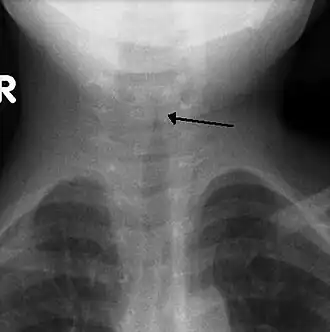

| Sinal do campanário observado em uma radiografia torácica de uma criança com a doença. | |

A radiografia frontal do pescoço não é rotineiramente realizada,[10] mas se for feito, pode mostrar um estreitamento característico da traquéia, chamado sinal de campanário, por causa da estenose subglótica. O sinal do campanário é sugestivo do diagnóstico, mas está ausente em metade dos casos.[15]